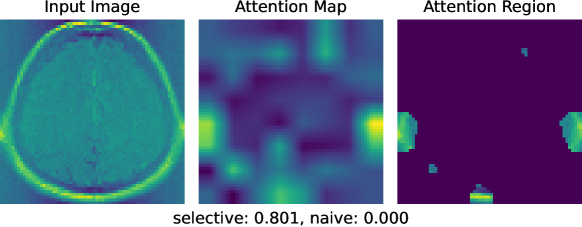

Figure 1 illustrates the problem setup considered in this study, where we applied a naive statistical test, which does not consider selection bias, and our proposed statistical test to brain image diagnosis task. The upper panel shows a brain image with a tumor region, in which we want the attentions to be declared as statistically significant (with a small -value). Here, both the naive test and the proposed test conclude that the identified attention is statistically significant with -values nearly 0. In contrast, the lower panel displays a brain image without tumor regions, in which we want the attentions to be determined as statistically not significant (with a large -value). In this case, the naive test falsely detects significance (false positive) with an almost zero -value, while the proposed method yields a -value of 0.801, concluding that it is not statistically significant (true negative).